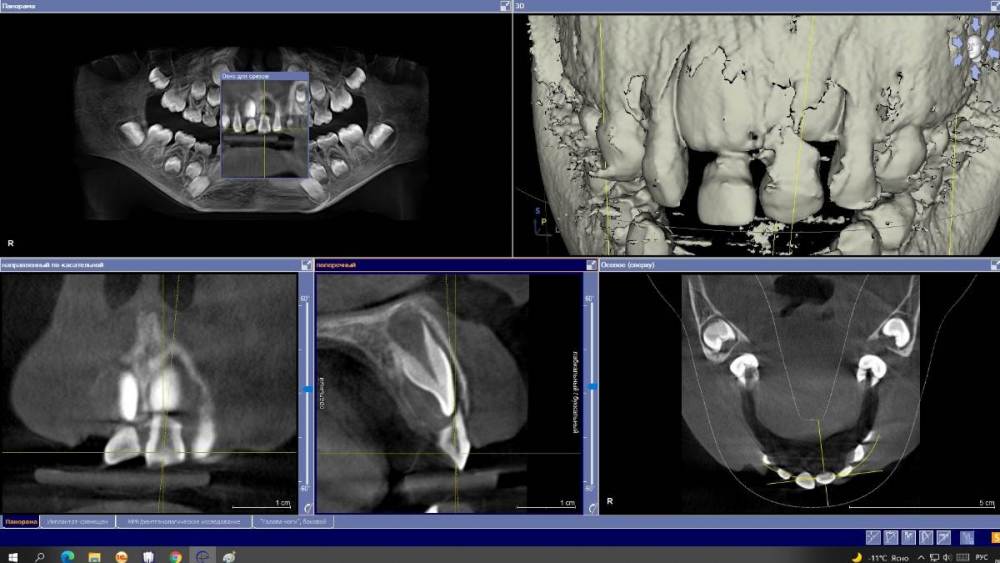

Ponchik Опубликовано 9 декабря, 2021 Поделиться Опубликовано 9 декабря, 2021 Пациентка 6.5 лет. Сегодня пациентка получила травму. Кожа губ без ссадин. Слизистая верхней губы с очень маленькими ссадинами. Центральные молочные резцы подвижны, при движении одного двигается и второй (по КЛКТ участок альвеолярного отростка между 51 и 61 сломан) круговая связка 51 вестибулярно сохранена (в акте дыхания почти участвует), у 61 сохранена полностью. Отмыл, пальцами на 1.5-2 мм выдвинул 5.1, переместил в правильное положение и приклеил на композит ленту на 4 резца (орто лигатур в клинике нет) Сижу теперь и думаю а нужно ли? Корни почти резорбировались. Смена не за горами. PS. Анамнез отягощен - пациентка моя дочь, действовал не автопилоте, детский приём не веду ни в какой форме. Может удалить резцы? Или оставить, но вдруг воспаление? Переход воспаления на зачатки постоянных и т.д. Что делать? Ссылка на комментарий